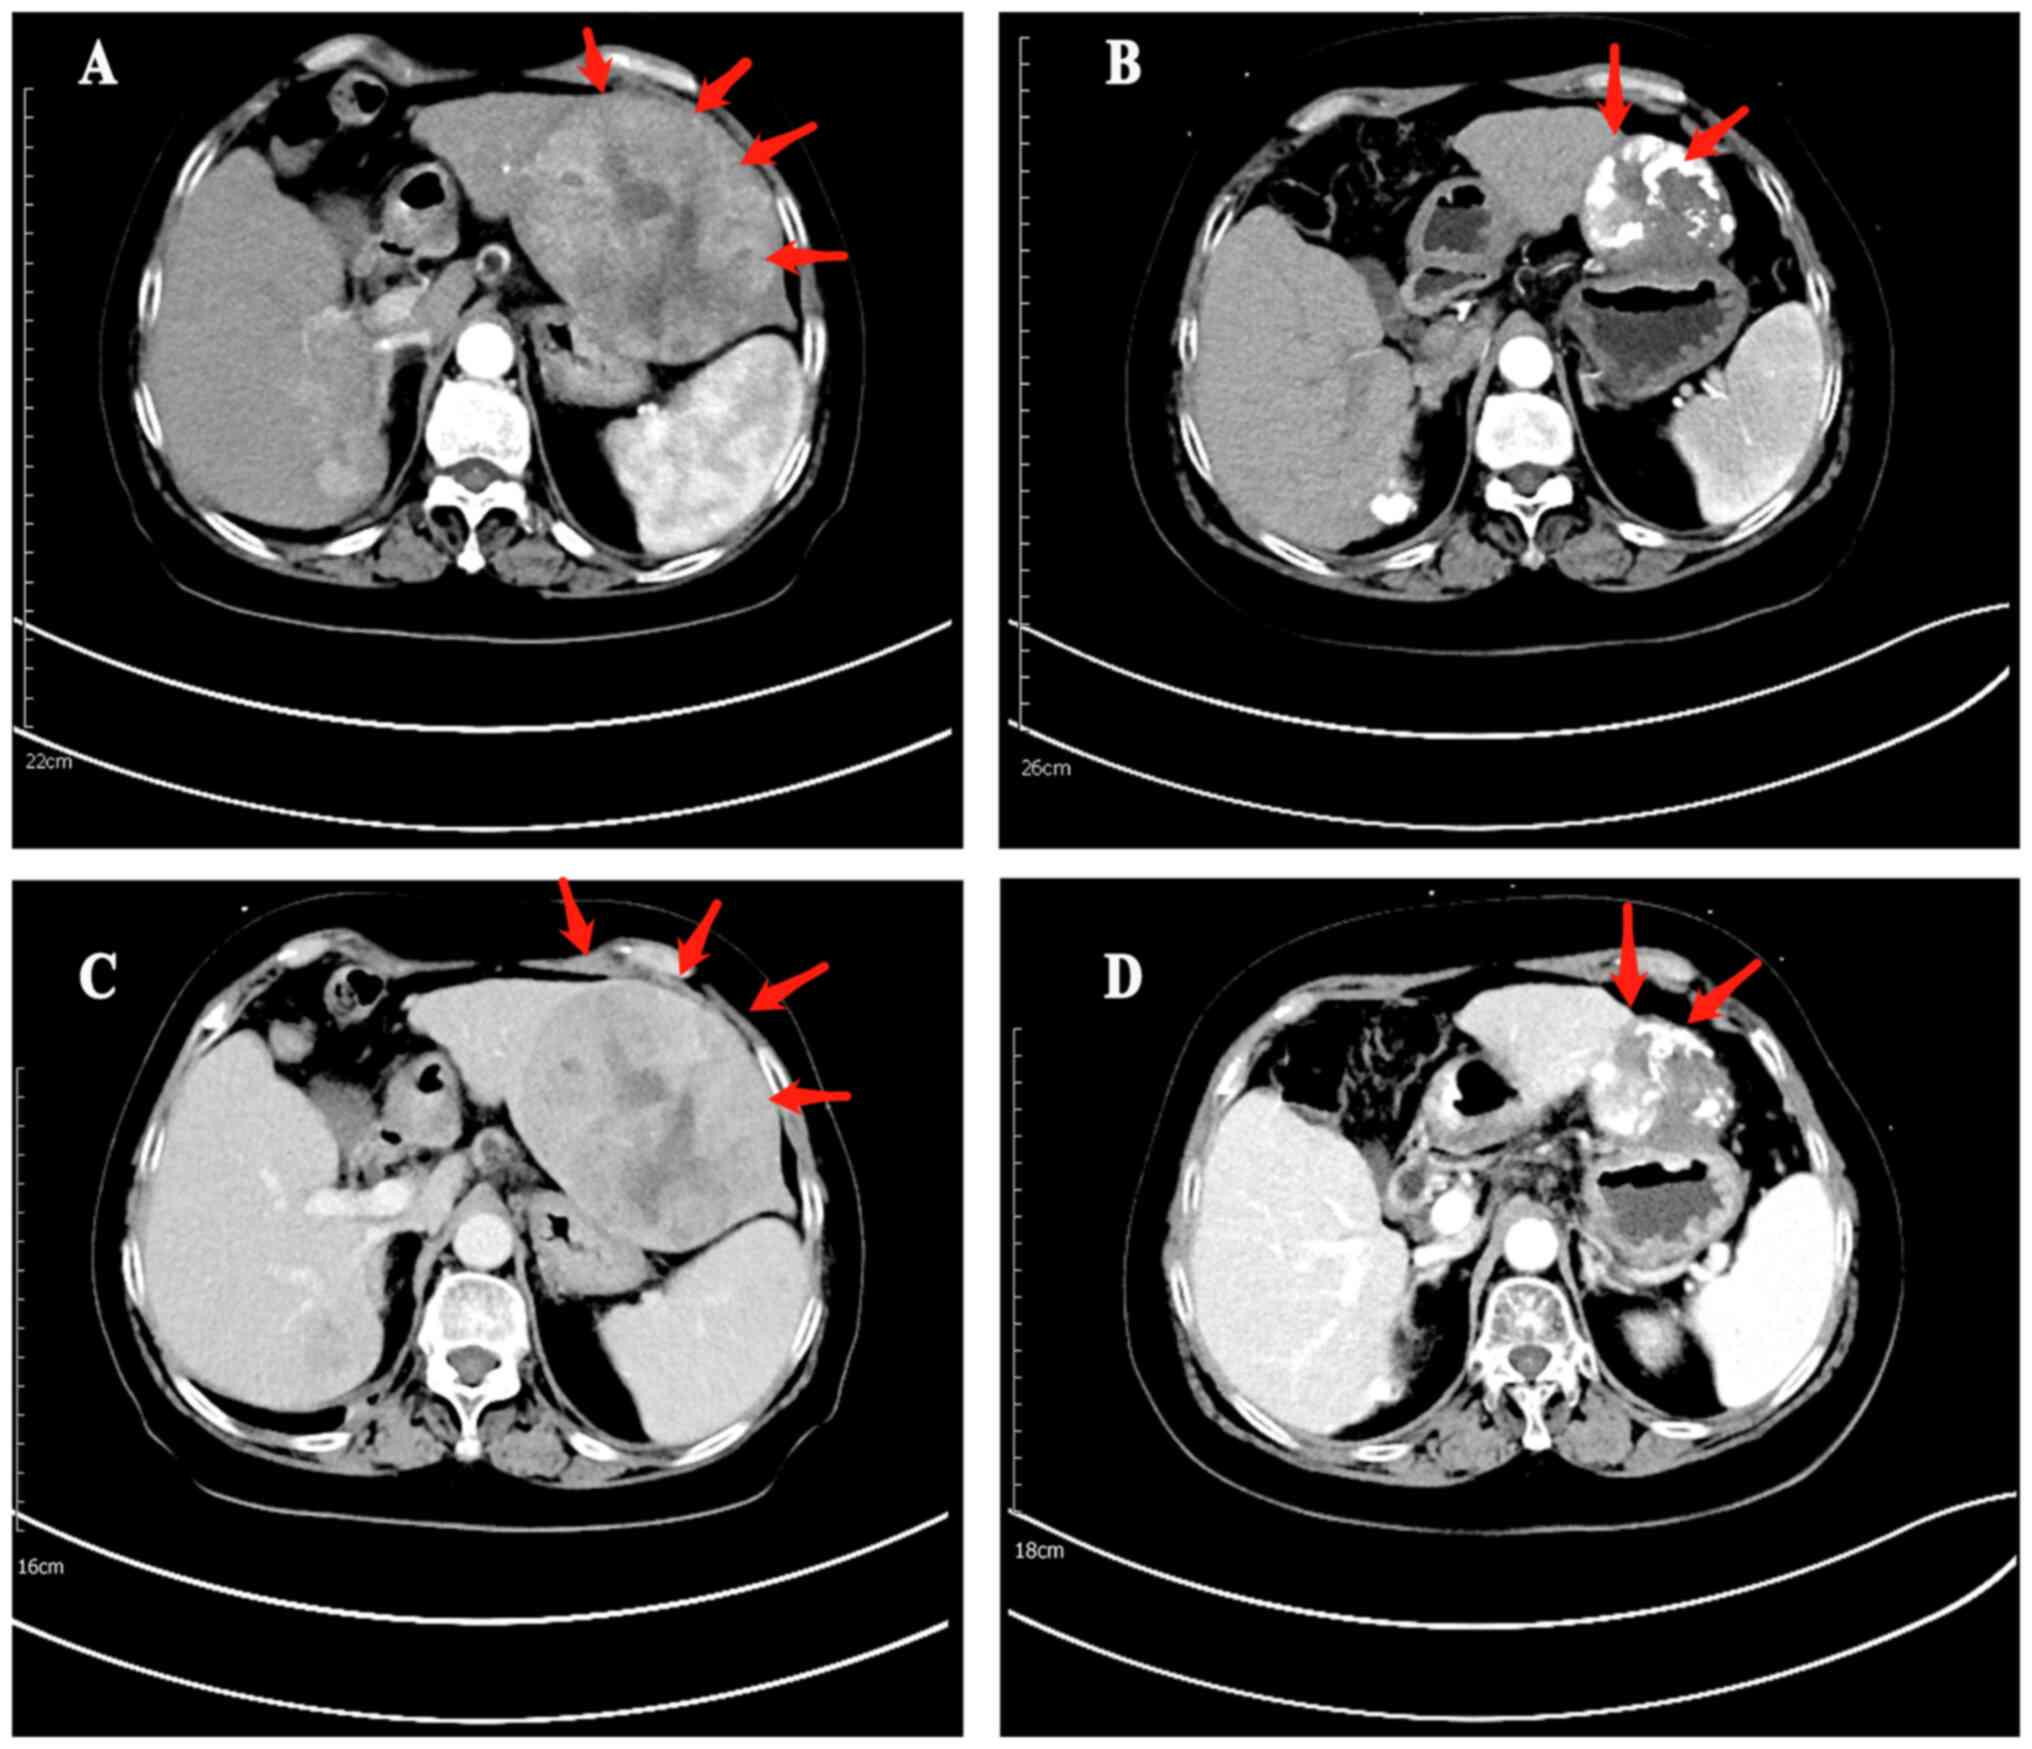

Based on the mRECIST criteria, four and 18 patients exhibited CR and PR, respectively after receiving Len + TACE, and two and nine patients, respectively after TACE (Table III). The ORR in the Len + TACE group was significantly higher compared with that in the TACE group (64.7 vs. 34.4%; P=0.014). Furthermore, DCR was markedly increased in the Len + TACE group compared with the TACE group (79.4 vs. 59.4%; P=0.066). Representative images of necrosis and regression of tumor lesion are shown in Fig. 4.

Figure 4.

Enhanced CT images in arterial phase of tumor lesions (A) before Len + TACE combination therapy (B) and necrosis and regression of the tumor lesions after Len + TACE combination therapy. Enhanced CT images in portal venous phase of tumor lesions (C) before Len + TACE combination therapy (D) and necrosis and regression of the tumor lesions after Len + TACE combination therapy. Len, lenvatinib; TACE, transarterial chemoembolization; CT, computer tomography.